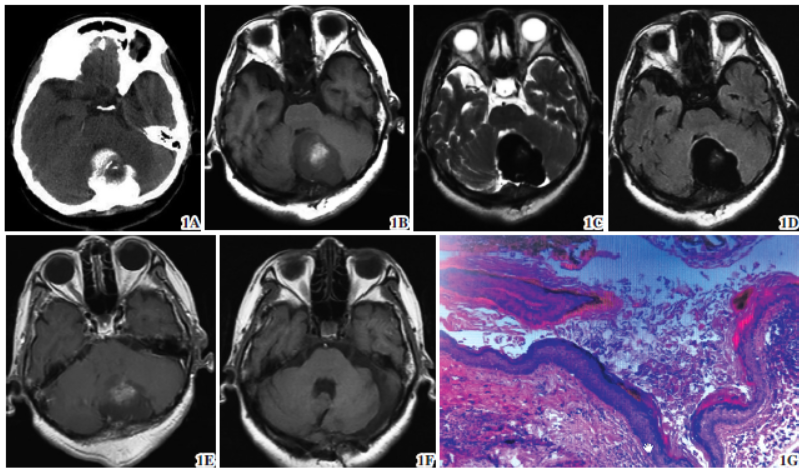

图1 颅后窝畸胎瘤。1A 术前头颅CT 示颅后窝不规则形高密度影;1B~1E 术前MRI 颅后窝混杂信号影,FLAIR呈低信号,强化不明显;1F 术后3 个月MRI 肿瘤无复发;1G 镜下见部分鳞状上皮、角化物及纤维组织,考虑成熟囊性畸胎瘤(苏木精-伊红染色× 100)